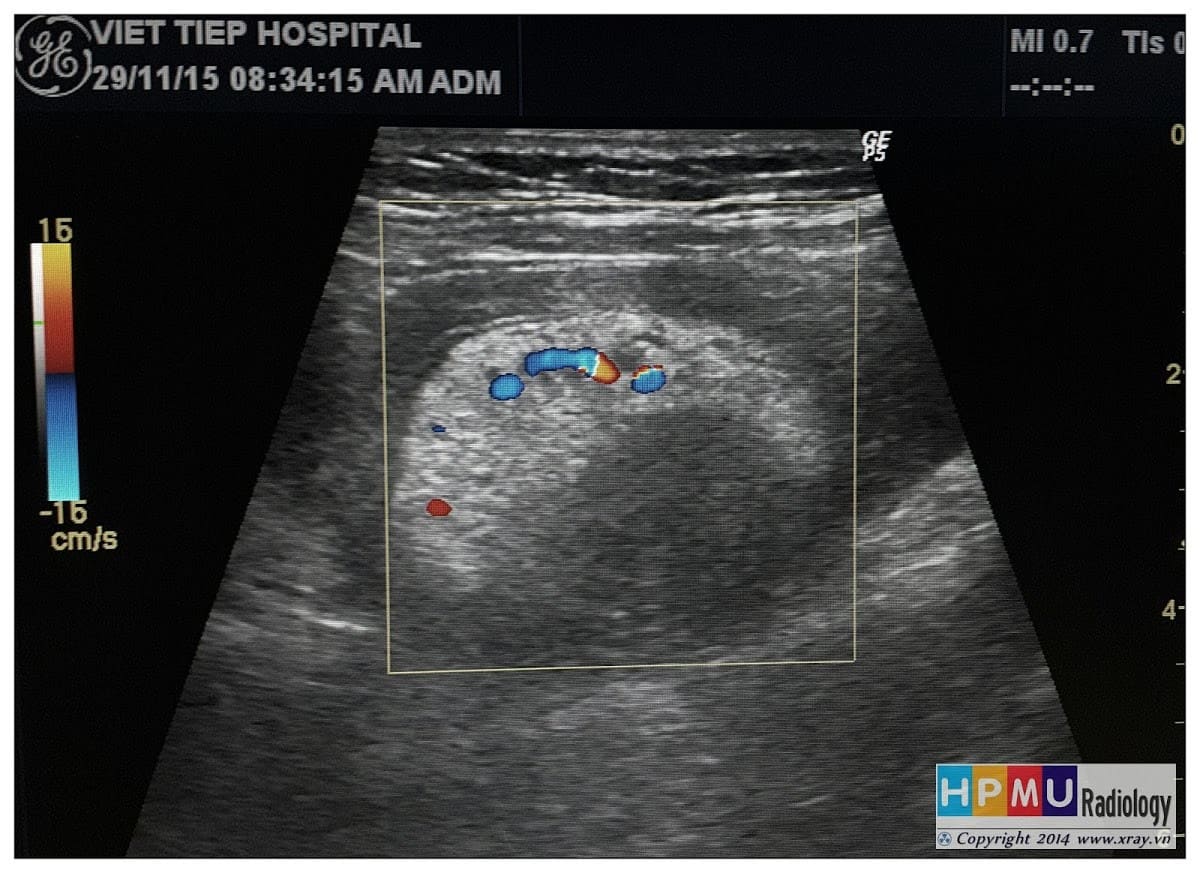

Lồng ruột

» Thông tin: Nam giới – 75 tuổi.

» Lâm sàng: Đau hố chậu phải + Bí trung tiện.